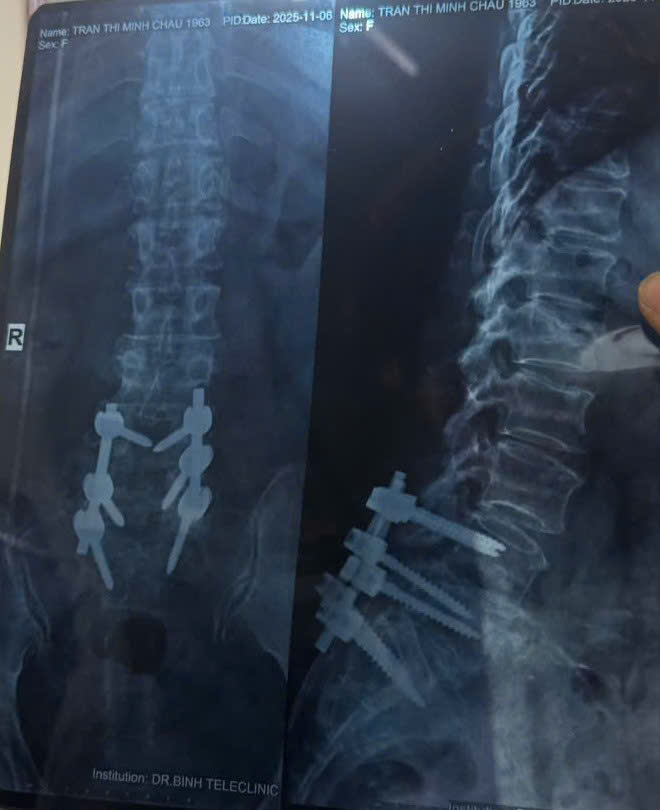

Hình ảnh phim chụp của bệnh nhân vào tháng 11/2025. (Ảnh: BSCC)

Bệnh nhân được tư vấn mổ từ tháng 11/2024. Sau nhiều lần giải thích cặn kẽ, bệnh nhân quyết định phẫu thuật vào ngày 6/1/2025. Kết quả sau mổ khiến chính bệnh nhân thay đổi hoàn toàn suy nghĩ.

Sau phẫu thuật và tập phục hồi chức năng, chỉ vài tuần sau Tết, bệnh nhân đã có thể đi lại, sinh hoạt và đón khách. Đến tháng 3/2025, sức khỏe tổng thể cải thiện rõ rệt. Tháng 11/2025, bệnh nhân tái khám định kỳ, gửi lại phim X-quang cột sống.